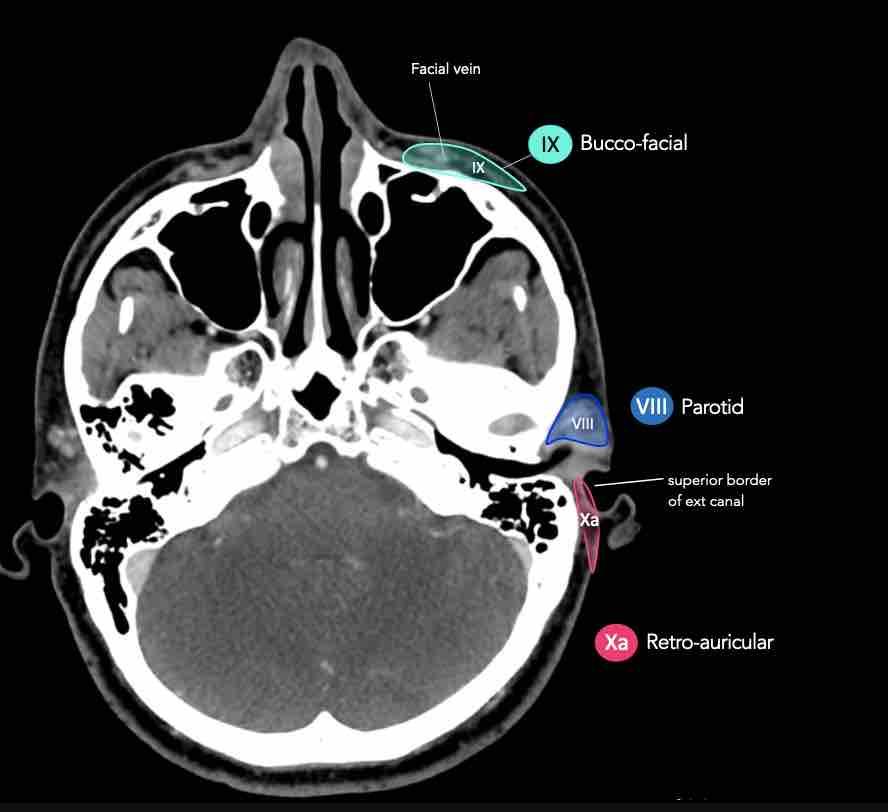

CT Scan Mặt Cắt Ngang (Axial CT)

Các lát cắt CT mặt phẳng ngang tương ứng với hình minh họa tổng quan.

Các lát cắt CT mặt phẳng ngang với hình ảnh chi tiết hơn.